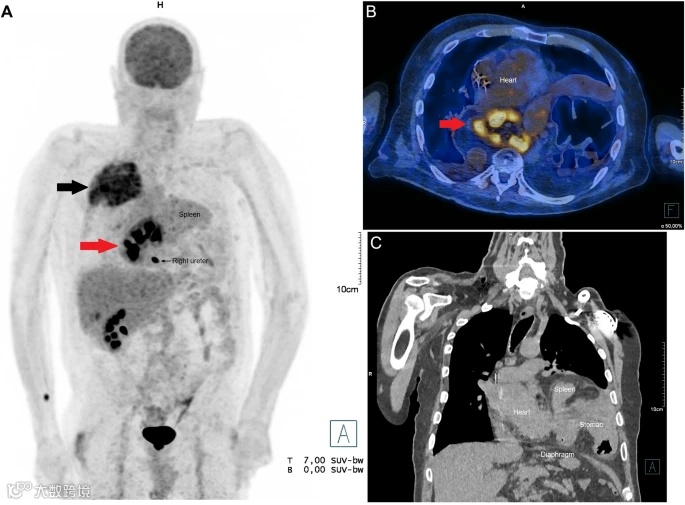

这次入院,是因为右肺上叶的一枚结节,胸外科怀疑是肺癌。为了分期,他被安排做了一次18F-FDG PET/CT。一切都在常规中进行,直到影像拉近,所有人的目光都被一块纵隔后的高代谢异常影吸引(图1)。

它躲在心影之后,不大,却在PET上闪着显眼的“热”。第一反应是——转移?更危险的,是淋巴瘤?还是纵隔肿瘤?

Claude医生开始追踪那块高代谢影的下缘,在多幅融合图像中,他找到了答案:一条弯曲的线,向下蜿蜒。它不是肿瘤的血供,也不是纵隔的静脉通路,而是——一根输尿管。它来自纵隔的“肿物”,最终连入膀胱。这不是肿瘤,这是一个错位的器官,一个异地隐居了87年的肾脏。

纵隔高代谢病灶?不,是Bochdalek疝所致的胸腔内肾脏(intrathoracic kidney)。

Bochdalek疝是一种源于胚胎第8周膈肌后外侧未融合的先天性畸形,在成人中极为罕见,发病率估计在0.17%至6%之间,左侧更为常见。在婴儿中,它通常表现为严重的呼吸困难和紫绀,而在成年人群体中,多数病例症状隐匿或仅有轻微不适,如间断性胸痛、腹胀、功能性消化不良等。本例中,患者的左肾完整地疝入纵隔,呈现高FDG代谢,是由于肾组织自身正常的代谢特征。